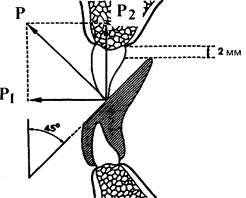

При конструировании наклонной плоскости необходимо помнить, что сила, оказываемая ею на резцы

верхней челюсти, направлена перпендикулярно последней. Нагрузку можно разложить по «правилу параллелограмма» на две составляющие: одну — направленную по оси зуба и внедряющую его, и вторую — направленную горизонтально и перемещающую зубы вперед. Величина каждой составляющей зависит от угла между наклонной и окклюзи-онной плоскостями. Для перемещения коронки резца вперед этот угол должен быть не менее 45°. Соответственно угол между продольной осью зуба и наклонной плоскостью равен примерно 30° (рис. 13.51).

Рис. 13.51. Разложение сил, образующихся при лечении небного положения резцов аппаратом с наклонной плоскостью.

P1 — составляющая, направленная горизонтально вперед; P2 — составляющая, направленная вертикально; Р — равнодействующая этих сил.